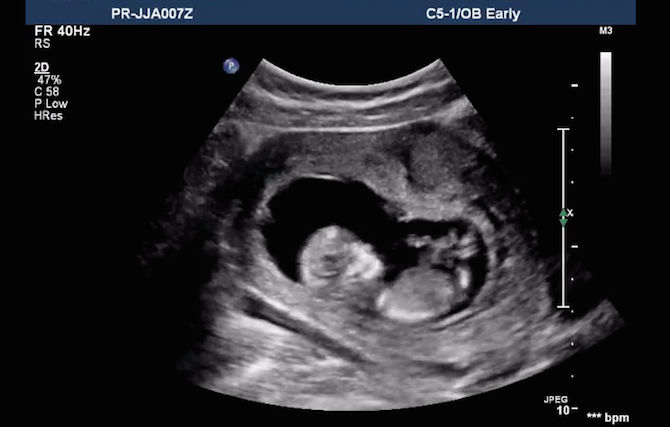

Jika anda ingin melihat si kecil melompat aktif dalam kandungan ketika membuat pemeriksaan scan kandungan, apa yang anda boleh buat adalah ketawa!